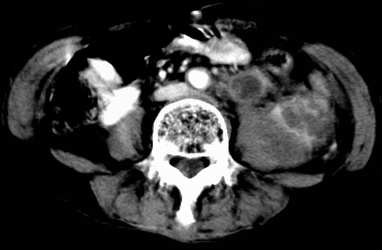

病患,女,69岁,左侧腰部不适,偶感疼痛2个月余,无化验室检查,行彩超发现左侧肾区实质性肿物,后行ct检查,结果同上。

左肾不规则软组织肿块,内见低密度坏死区,与正常肾实质分界不清,左肾明显增大,增强呈不规则条索状强化,肾盂及左输尿管上段扩张。肾周脂肪层受侵、模糊。印象:典型左肾癌。

平扫,表现为肾实质肿块,呈分叶状,肿块密度不均,内有不规则低密度区(陈旧性出血?坏死?)有的似呈囊性,增强明显不均一强化,与肾实质相比呈相对低密度的不均一肿块,肾周脂肪间隙可见,肾前筋膜未见增后,肾血管及腹主动脉旁未见肿大淋巴结影

左侧肾癌并肾静脉癌栓.腹膜后淋巴结肿大转移.

顺便说几句。肾癌的转移,肾静脉的转移尤为常见,他可以顺沿静脉直至下腔静脉,这种转移,临床中也不少见,笔者遇到过数例。这种转移对于临床来说有较大意义,直接影响手术的成功、手术的方式等,临床有不少肾癌切除术后,静脉残端复发病例。不知楼主有意还是无意,没有给静脉期,或者左肾静脉充盈的图象。

三期抓的不错,典型的肾癌,且已累及肾盂及左输尿管上段

左肾癌累及左输尿管,左肾静脉无受累征象。